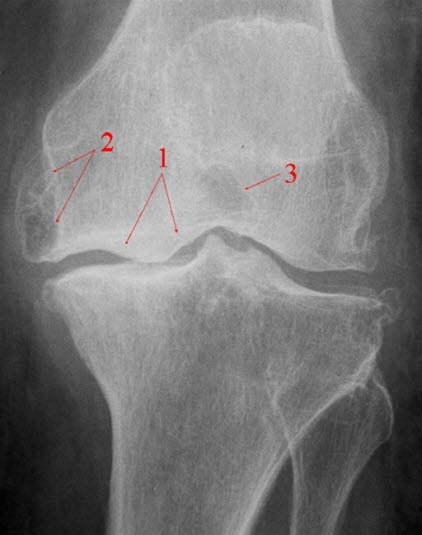

Se røntgenbilde av kneleddet forfra og fra siden.